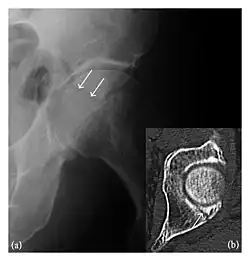

Occult osseous injuries may result from a direct blow to the bone by compressive forces of adjacent bones against one another or by traction forces during an avulsion injury. Lesions in the tibial plateau, hip, ankle, and wrist are often missed. In a tibial plateau fracture, any disruption of the posterior and anterior cortical rims of the plateau should be sought. Impaction of subchondral bone will appear as an increased sclerosis of the subchondral bone (Figure 1). In the hip, posterior acetabular fractures also present subtle radiographic findings. The acetabular lines should then be carefully examined keeping in mind that the posterior rim, which is harder to see on X-rays, is more frequently fractured than the anterior rim (Figure 2). In the wrist, detection of carpal bone fractures is often challenging, with up to 18% of scaphoid fractures radiographically occult. Carpal fractures, especially the scaphoid, are associated with the risk of avascular necrosis. In apparently normal wrist radiographs from symptomatic patients, if there is history of a fall on an outstretched hand with pain in the anatomic snuffbox, suggesting scaphoid injury, the initial examination with posteroanterior, lateral, and pronation oblique views must be complemented by other specific views such as supination oblique and the "scaphoid" view A careful examination of cortices for evidence of discontinuity or offset and cancellous bone for lucency is necessary (Figure 3).[1]

Figure 1: A 56-year-old woman presenting with left knee pain after a fall. (a) Initial anteroposterior radiograph was considered normal, however, subtle cortical disruption of the anterior rim of the medial tibial plateau, medial to the tibial spine, is noted (arrow). (b) Coronal T1-weighted MRI confirms the cortical disruption (arrow) and shows extensive fracture through the proximal tibia. (c) Coronal proton density-weighted image with fat saturation shows extensive edema in the subchondral bone. Note also hypersignal adjacent to the medial collateral ligament corresponding to a grade I sprain (arrowheads).[1]